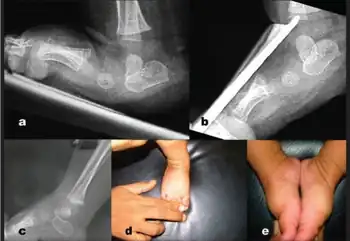

a) Lateral X-ray right foo with congenital vertical talus shows irreducible talonavicular joint. b) stress plantar flexion view shows fixed plantar flexed talus c) follow up X-ray- reduction of talonavicular joint with the track of k-wire in talar body d,e) photograph showing good correction of foot deformity